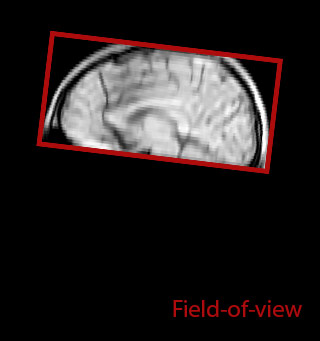

of limiting MWI to the brain, even without the cerebellum, we can now spend about the same amount of time and scan the whole brain and the cervical spinal cord, which is a huge boost for us.” Dr. Rauscher says, “For MWI we perform 3D T2 with 32 or more echoes. This used to take a long time, but with Compressed SENSE we can decrease this to ten minutes for the whole head. Because of the large field of view (FOV) on the readout direction, we even get information from the brainstem, which we previously missed when we were using the GRASE approach. Having the whole head scan is nice because it has spatial resolution, orientation and FOV that are comparable to the standard 3D clinical MS scans, including the FLAIR and 3D T2, and a 3D T1 for brain volume.”

Smaller, more isotropic voxels

Excellent detail in quantitative maps

For instance, we can get the combined information from looking at advanced diffusion, multi-shell diffusion combined with myelin water, and then also add quantitative susceptibility mapping and get a better idea of tissue micro structure effects from all three combined. On the old scanner we only had time to run maybe one or two of these sequences in addition to the conventional scans,” says Dr. Rauscher.

Accelerating scans helps researchers achieve their imaging goals

He says the accelerated scanning is achieved via the use of Compressed SENSE and MultiBand SENSE. “We can use Compressed SENSE acceleration factors of about 10 on a 3D FLAIR for instance, which is quite remarkable compared with what we saw with the Achieva. With 3D FLAIR, we can push the spatial resolution to 0.3 cubic mm and it works. Previously, our 3D FLAIR scans lasted about 8 minutes, but now with Elition they are five minutes. The SNR is also visibly better. Our SWI and QSM scans look fantastic. Also, since a lot of neuroimaging is EPI based, using the MultiBand SENSE technique can increase temporal resolution and make it possible to run complicated DTI scans relatively quickly.”